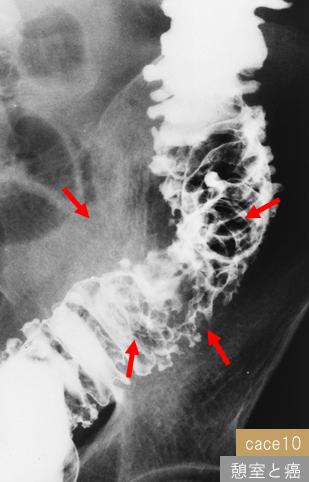

部位(臓器別)大腸/下行

検査方法X-P

腫瘍の肉眼分類1型(腫瘤型)/

病変の最大径(ミリ)30〜34

腫瘍の深達度ss(a1)